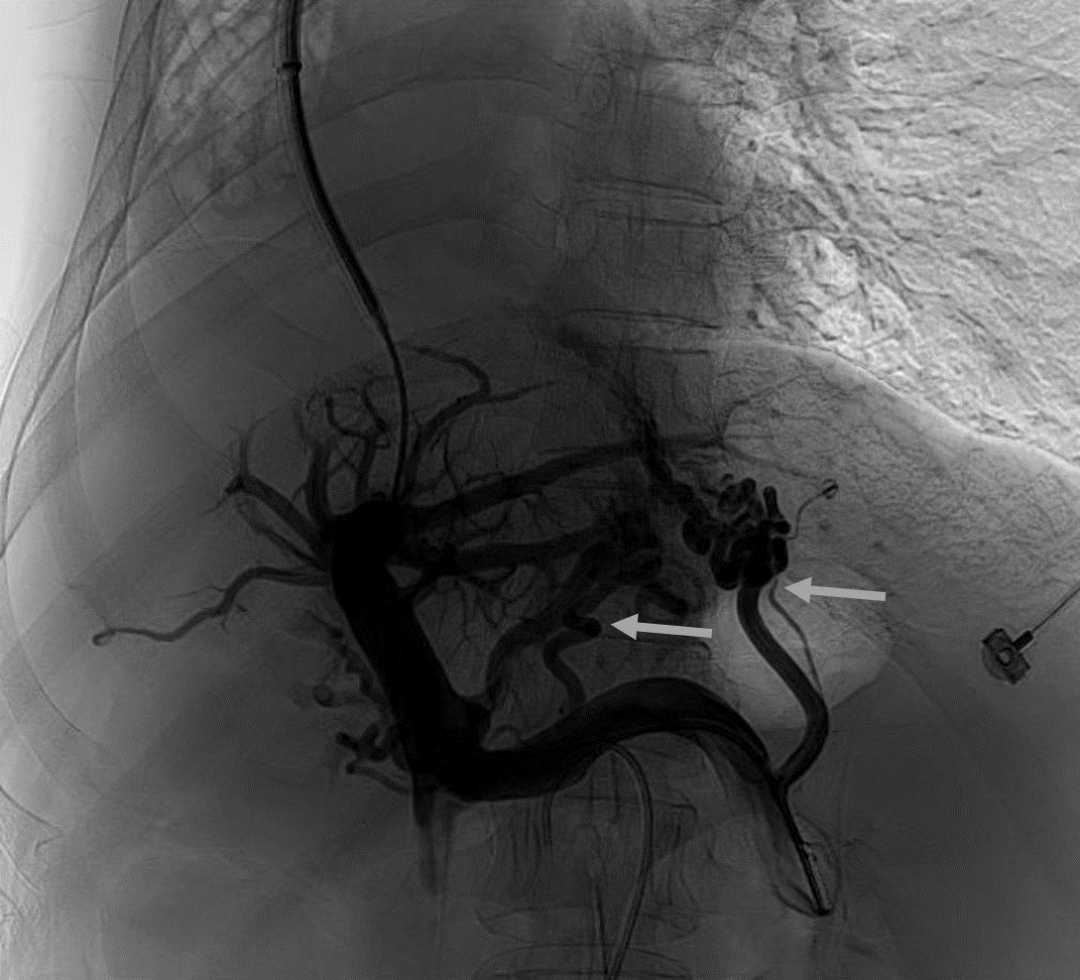

韓國宏教授介紹,TIPS手術(shù)是通過在肝靜脈與門靜脈之間的肝實(shí)質(zhì)內(nèi)建立分流通道,通過降低門靜脈壓力來預(yù)防和治療因門靜脈高壓引起的食管胃底曲張靜脈破裂出血或頑固性腹水。該手術(shù)不用開刀、創(chuàng)傷小、操作過程復(fù)雜、技術(shù)難度大、安全風(fēng)險(xiǎn)高,是目前外周血管介入中難度最大的手術(shù)之一。再加上人群中右位心發(fā)病率極低(約萬分之一),經(jīng)查閱文獻(xiàn),在國內(nèi)外尚未有類似病例報(bào)道,無經(jīng)驗(yàn)參考。在右位心基礎(chǔ)上行TIPS術(shù),無疑是難上加難。我們反復(fù)研究患者肝臟及心血管的特殊情況,詳細(xì)討論了手術(shù)方案,決定放棄常規(guī)的肝靜脈穿刺,另辟蹊徑,選擇高難度高風(fēng)險(xiǎn)的肝后段下腔靜脈穿刺門靜脈左支,憑借多年的經(jīng)驗(yàn)和嫻熟的技術(shù)最終成功的在下腔靜脈與門靜脈之間放置了TIPS專用支架,術(shù)后門靜脈壓力梯度從術(shù)前的19mmHg降至3mmHg,曲張靜脈消失,解決了困擾曹女士多年上消化道出血的困擾?;颊咝g(shù)后第二天即可正常下床活動(dòng)。